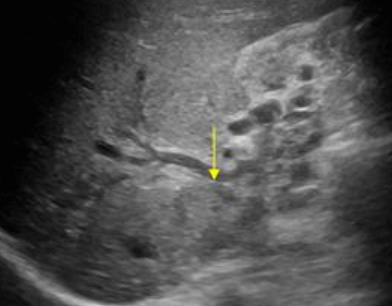

Choledocholithiasis US finding

- 총담관 내에 후방음향음영을 동반한 강한 에코가 관찰된다.

- 총담관의 확장 소견이 보인다. ( 7mm 이상)

- 담석이 관찰되지 않고 간외, 간내담관의 확장소견을 시사하는 엽총징후(shotgun sign)이나 평행관 징후(parallel channel sign)가 관찰되기도 한다.

- 엽총징후(shotgun sign): 간외 담관이 확장되어 간외 담관과 문맥이 이웃해 관찰된다.

- 평행관 징후(parallel channel sign): 간내 담관이 확장되어 인접하고 있는 문맥과 나란히 2개의 관상구조로 나타난다.